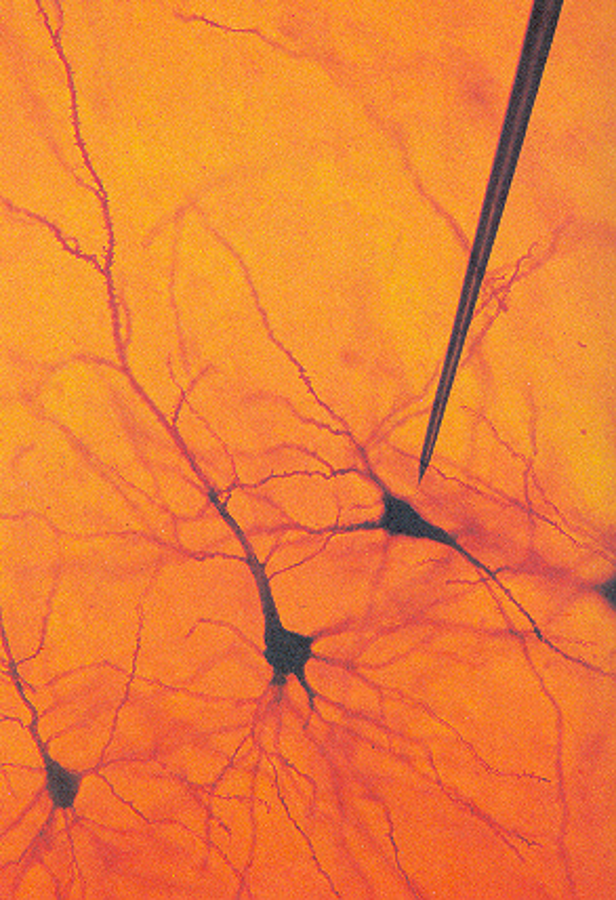

what is N

neurons

ependyma

astrocyte

microglia

oligodendrocyte